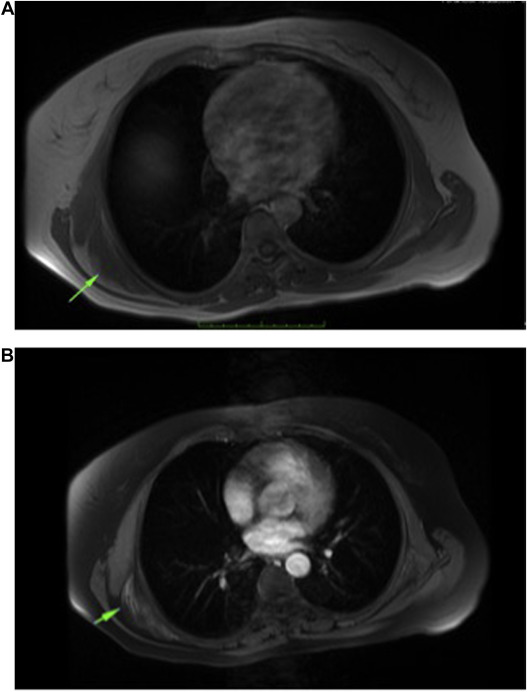

MRI was the most important diagnostic tool in this study (Fig. 5 ). Although lesion may be underdiagnosed radiologically, Malghem et al described a non-encapsulated lesion in typical location between fibrous tissue and fat tissue that showed an alternating pattern on MRI. While fibrous tissue showed low signal intensity in T1 and T2 sequences, fat tissue showed high signal intensity in T1 sequence. The areas that enhance or do not enhance can be seen in contrast series. Fat tissue is seen as lines in fibrous tissue parallel to chest wall.15 One study categorized ED into 3 subgroups based on MRI findings. Type A is inhomogeneous, fasciculated type; type B is inhomogeneous, non-specific type; and type 3 is isointense type with homogeneous muscle. Average positive predictive value and sensitivity were found to be 93.3% and 100%, respectively.16 US is 1 of the diagnostic modalities used in typical cases. A well-demarcated multilayer eco-signal is noted.17 Studies conducted using positron emission tomography/computed tomography (PET/CT) found that ED had a diffuse but slight 18F-fluorodeoxyglucose involvement. Studies found average standardized uptake value to be 2.29.18 Blumenkrantz found 1.66% ED in 1751 patients undergoing PET/CT.19

Fig. 5. (A) Axial T1 sequence shows isointense mass between scapula and thoracic wall. (B) Heterogenous contrast enhancement of lesion in T1 fat saturation sequence.